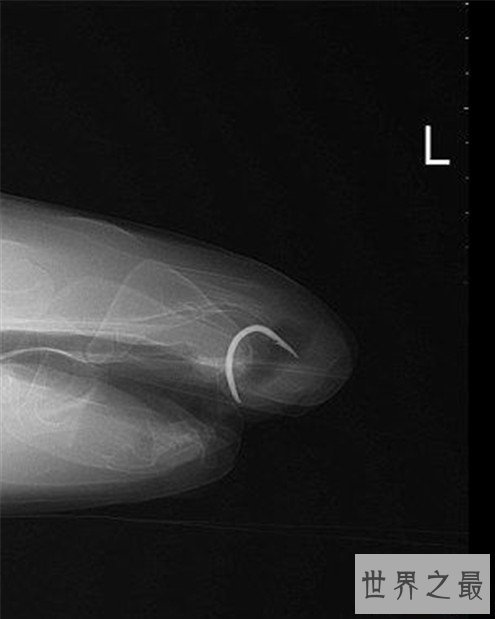

但是他的身材并不像是不喜欢实物那种,所以研究的人就把他带回来进一步做观察才发现,他的嘴里有一个鱼钩卡住了,这应该是他不想进食的主要原因,而研究人员看着鱼钩的情况,也发现这个鱼钩应该卡在这里很久了,都生锈了,于是研究人员赶快把他的鱼钩取出来。

并做了后面的修复手术,才得以让弗洛伦斯重新开始进食,但没想到的是,他再也不吃肉来了,估计是因为那个鱼钩给他造成了心理阴影,他上次应该也是因为贪嘴,吃了里面有鱼钩的肉类,让鱼钩卡在了自己嘴里,这让他以后再也不敢吃肉了,他怕再度被卡住,而研究人员现在也在尽快的恢复他原本吃肉的属性,如果他恢复不来,他和他的家族人员恐怕就难以相处了。